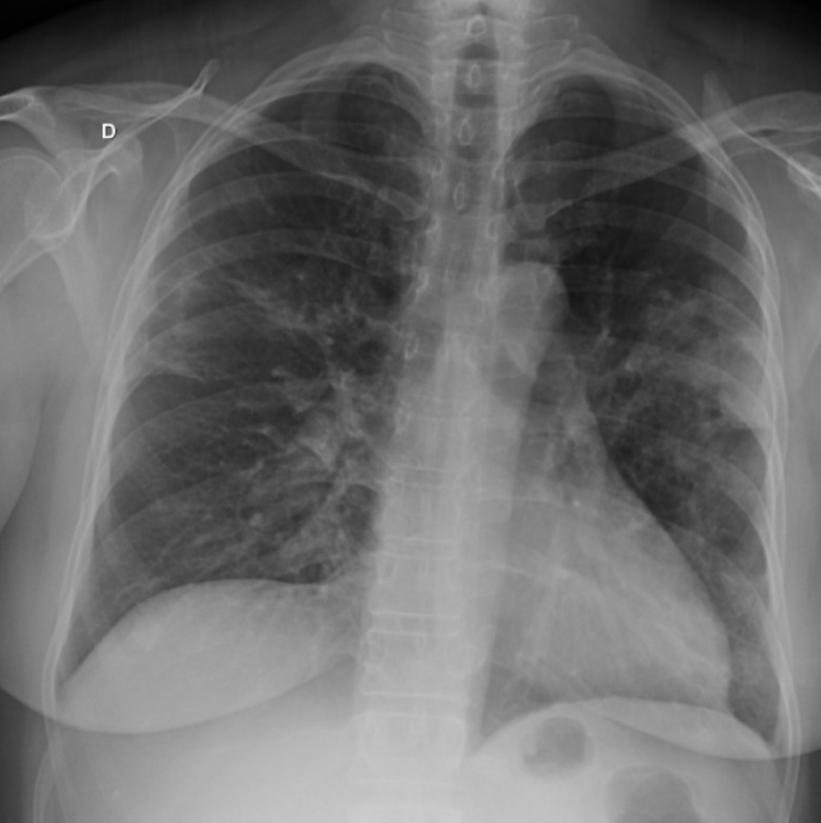

Refer to caption

Fig 2. Influenza